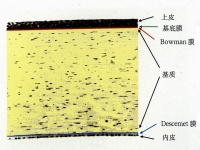

8.角膜血管的形成

角膜炎症常伴有血管增生,多呈网状,发生在溃疡附近的角膜缘。这些都是浅层

血管,但深部溃疡也有深层血管。初则血管向溃疡呈放射形推进,

当溃疡开始痊愈时即展宽。这一点对溃疡的痊愈极为重要。但也有时溃疡痊愈而无血管增生。溃疡愈合后血管渐即消失,但也有永不消失者,特别是在有虹膜前粘连时。

有时血管伴同炎症,类似渗出物,进入角膜,见于角膜实质炎和角膜血管翳时。确定血管的位置对于鉴别角膜病颇为重要,常可借之诊断角膜炎的类型。

新生血管可来自角膜缘的血管网或角膜缘较深层的血管,前者为浅层血管,直接与结膜血管相连接,一般呈弯曲的河流状,后者为深层血管,呈毛刷或扫帚状,不与结膜血管相连接,在角膜缘即终断。